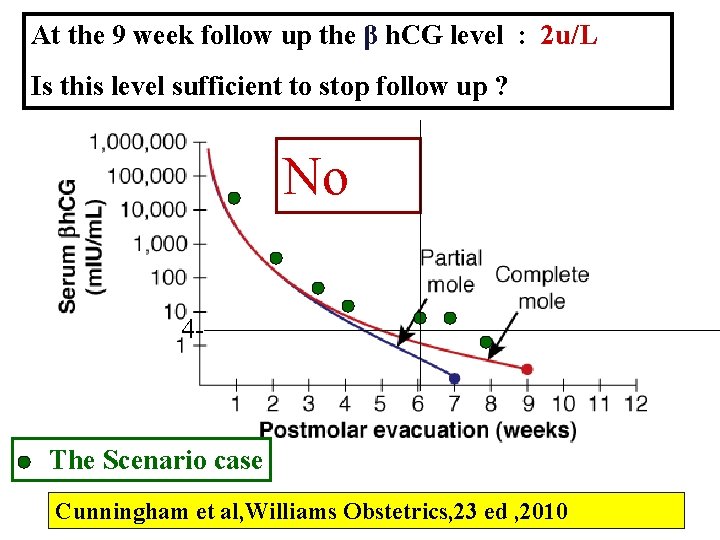

At the 9 week follow up the β h. CG level : 2 u/L Is this level sufficient to stop follow up ? No 4 - The Scenario case Cunningham et al, Williams Obstetrics, 23 ed , 2010